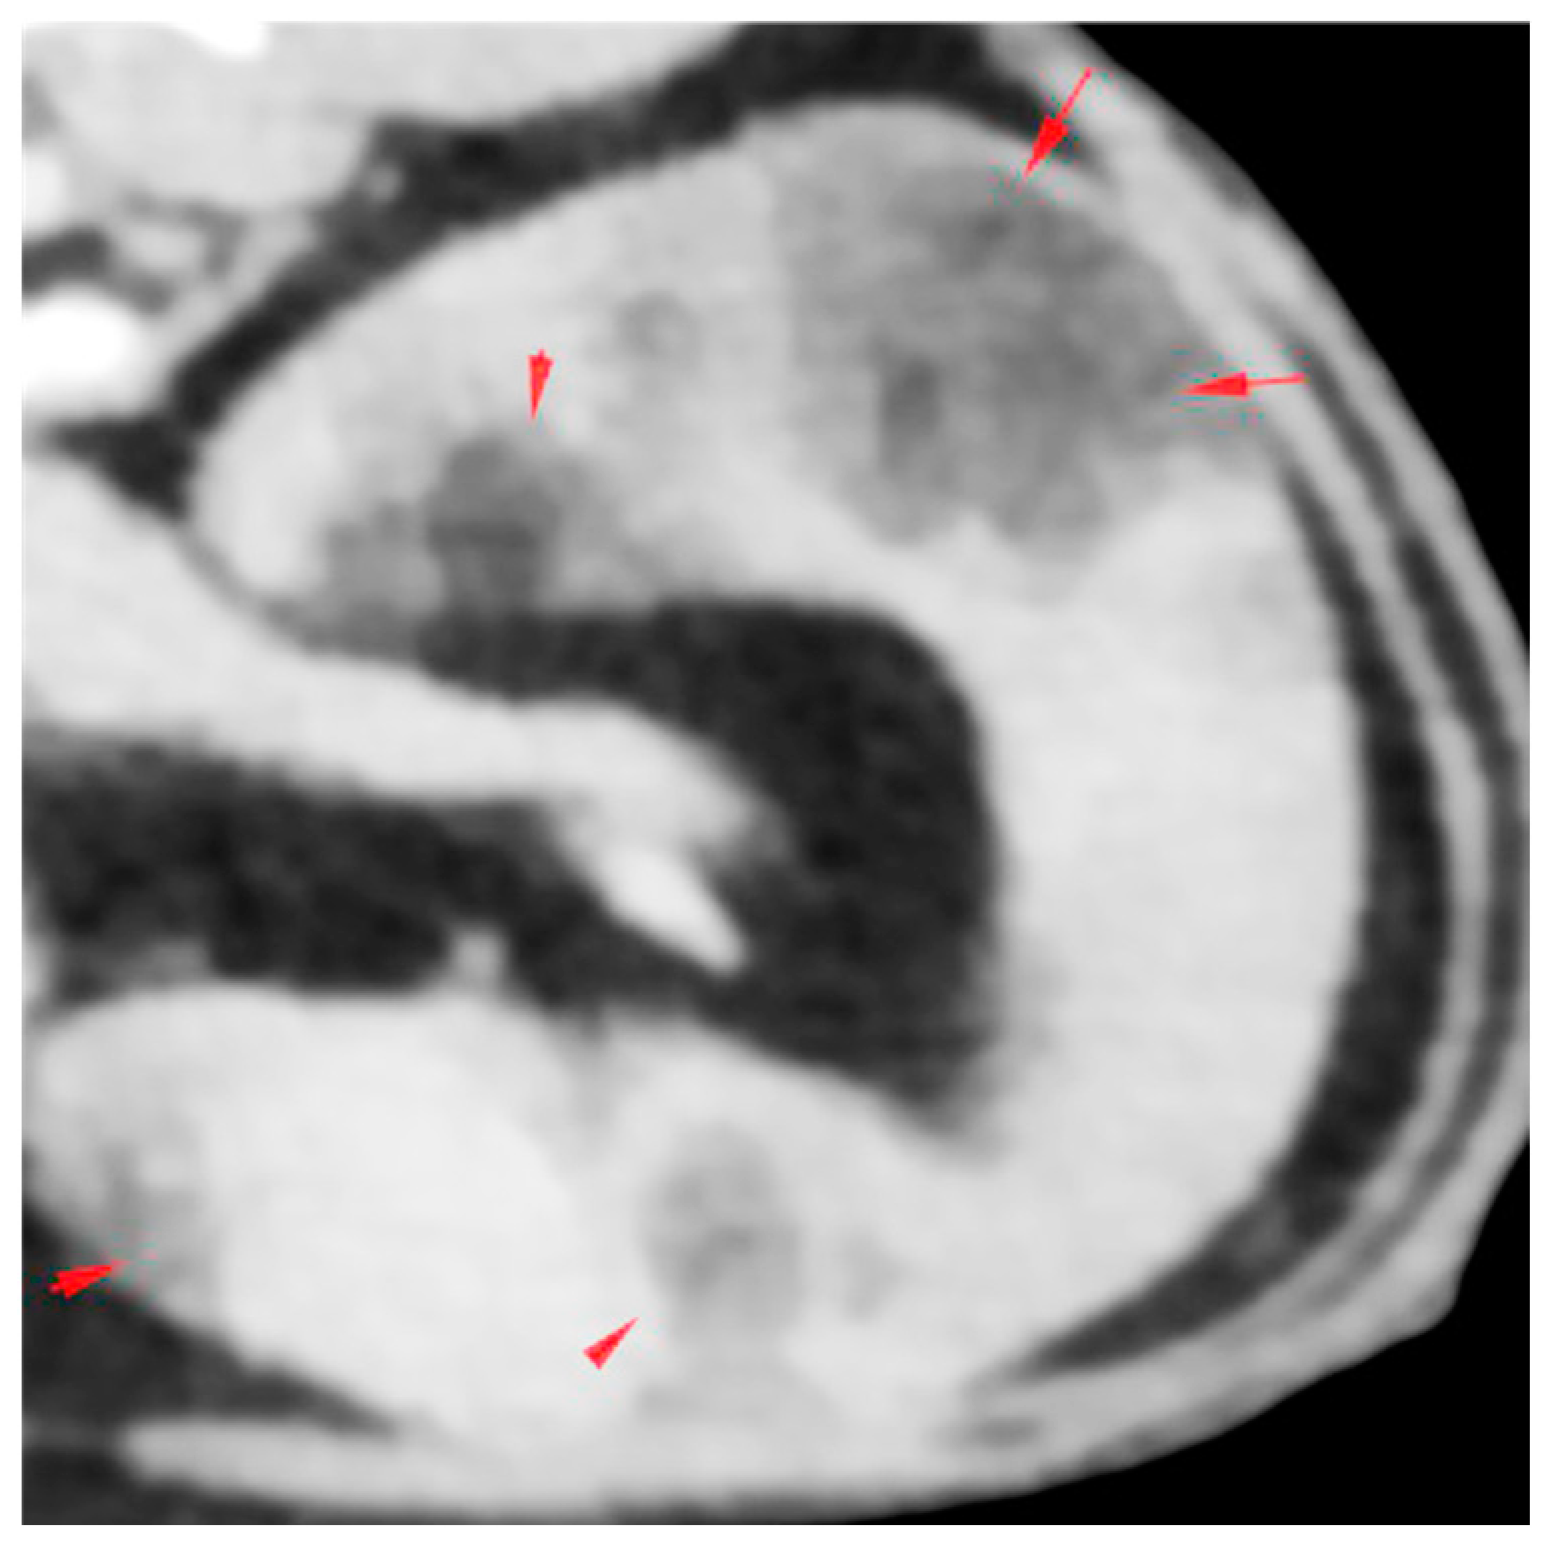

2.1. History, Clinical Findings and Diagnostic Investigations